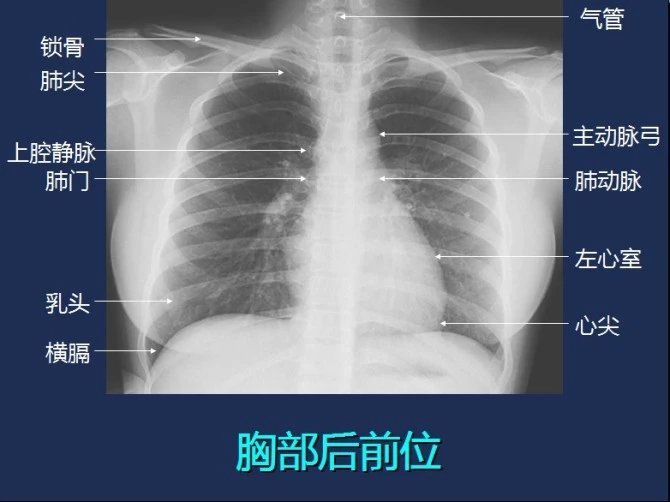

胸部影像解剖

图片尺寸1417x2034